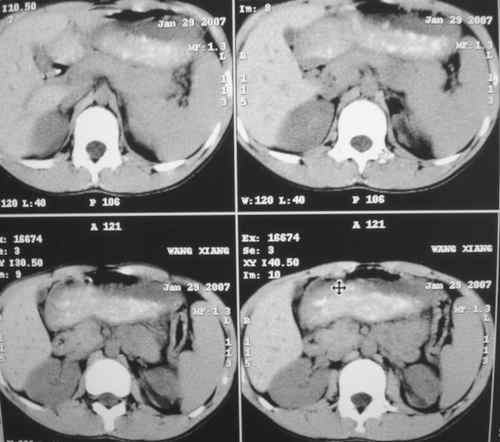

m 15y 外院b超发现左肾包块,遂来ct检查。

左肾外形明显小于右肾,左肾中上极后侧可见一等密度影,与肾分解不清,肾盂肾盏无扩张,先考虑:左肾发育不良,建议强化除外占位

左肾外形明显小于右肾,左肾中上极后侧可见一等低密度影,与肾分解不清,肾盂肾盏无扩张,先考虑:左肾发育不良,平滑肌脂肪瘤待排除。